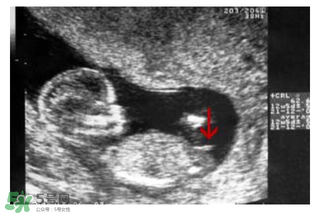

b超怎么看胎兒性別之看形狀

媽媽們可以在懷孕兩個(gè)月的時(shí)候去做B超,如果寶寶的形狀是長(zhǎng)型的,像茄子或長(zhǎng)條狀的,那么很有可能是男寶寶,若是橢圓或是圓型,那么可能是女寶寶。